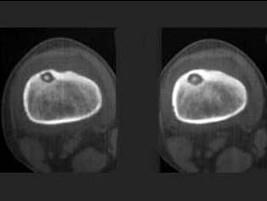

问题 男,36岁,左大腿以局部疼痛就诊,夜间疼痛加剧,请结合所提供的图像,选择最佳选项 ( )

选项 A、纤维性骨皮质缺损 B、非骨化性骨纤维瘤 C、骨样骨瘤 D、骨纤维异常增殖症 E、良性骨母细胞瘤

答案 C